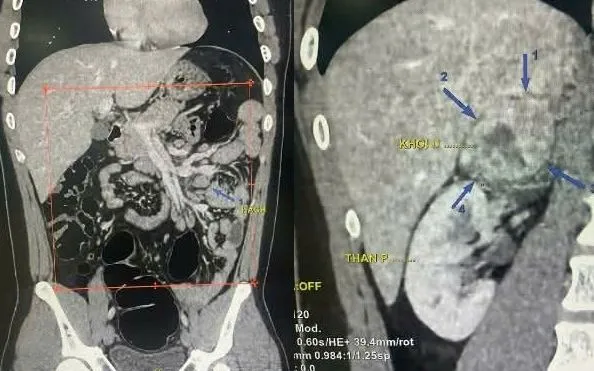

BSCKII. Trần Đăng Huấn - người trực tiếp khám, đã chỉ định chụp CT-Scanner ổ bụng có tiêm thuốc. Kết quả ghi nhận khối đặc thượng thận phải kích thước 58 × 52 × 44 mm, kèm nhiều hạch ổ bụng chưa loại trừ lymphoma và tình trạng gan nhiễm mỡ.